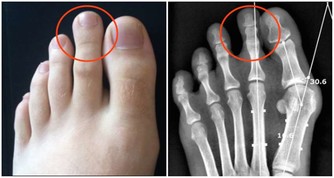

還有一個腎囊腫,我們經常去做體檢,可能某個大夫跟我們說,B超發現你腎上長了一個囊腫,2公分,3公分,會告訴你沒事兒,觀察就行。腎囊腫的發生,有的囊腫在剛出現的時候就已經是惡性的,所謂囊性的腎癌,發生的時候就是一個惡性的。只是剛開始可能比較小,長得比較慢,惡性程度相對比較低,所以容易被忽略。所以對於超過50歲的人來說,如果第一次發現囊腫,如果囊腫直徑超過2公分,建議大家還是應該去做一個核磁或者CT,明確一下囊腫的性質,有可能這個囊腫本身就是惡性的,這是第一個。

第二個,有一些腎囊腫是可以發生惡變的。尤其是長期透析的病人,可能會有一些獲得性的、醫源性的腎囊腫,這種腎囊腫容易轉化為惡性的。